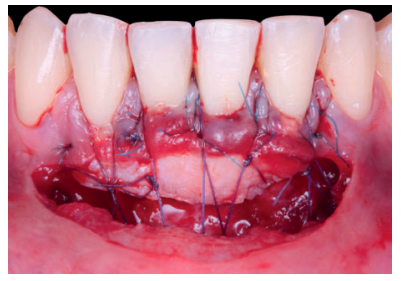

Una vez creado el lecho receptor, se procedió a la obtención de un ITC de la mucosa masticatoria palatina y a la sutura de dicho injerto mediante dos puntos colchoneros horizontales, uno situado en la parte mesial y otro en la parte distal del sobre. Para mayor adaptación y estabilización de las papilas se realizó un punto suspensorio cogiendo papila e ITC, mediante sutura de 6/0 no reabsorbible (Figura 3).

También, se realizó una sutura dentosuspendida para asegurar el injerto en posición apical, este punto se ancló en el periostio apical al injerto y suspendido alrededor de la cara lingual del diente con recesión mediante sutura de 5/0 reabsorbible. Se dejó cicatrizar por segunda intención en la base (zona de la vestibuloplastia).

Se realizó control a la semana de la intervención (Figura 4) y tras 15 días se retiró la sutura, observando la revascularización del injerto y la epitelización del área cruenta apical al sobre (Figura 5). Se realizó seguimiento al mes (Figura 6), a los 3 meses (Figura 7) y al año y medio del procedimiento (Figura 8).